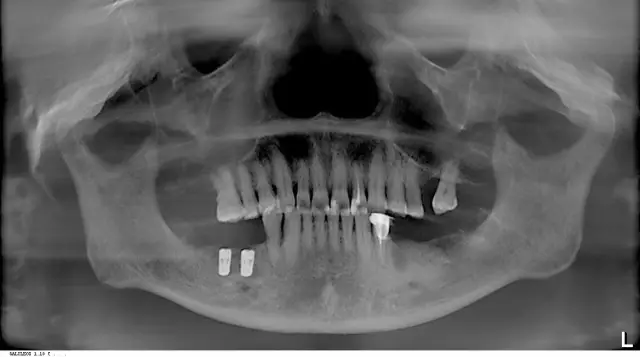

在全面的口腔结构及骨质情况扫描后,王汉禹院长为饱受牙齿口腔困扰的叔叔阿姨们,就志愿者邹女士的牙片具体分析了其牙齿问题:因邹女士长期使用安装烤瓷牙的左侧吃饭咀嚼,时间一长牙根开始疼痛到不能忍受,来就诊一检查是牙根断裂了。他提醒老年人在进行口腔保健和治疗时不要图一时的方便便宜,要从长期治疗效果考虑。

邹阿姨拔牙、种植后的牙片(先种一边,下次再种另一边)